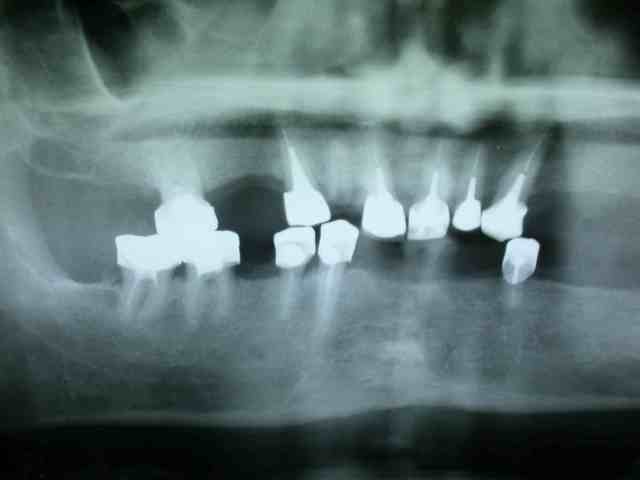

bon allez je vous mets la pano initial et je continue après.

.